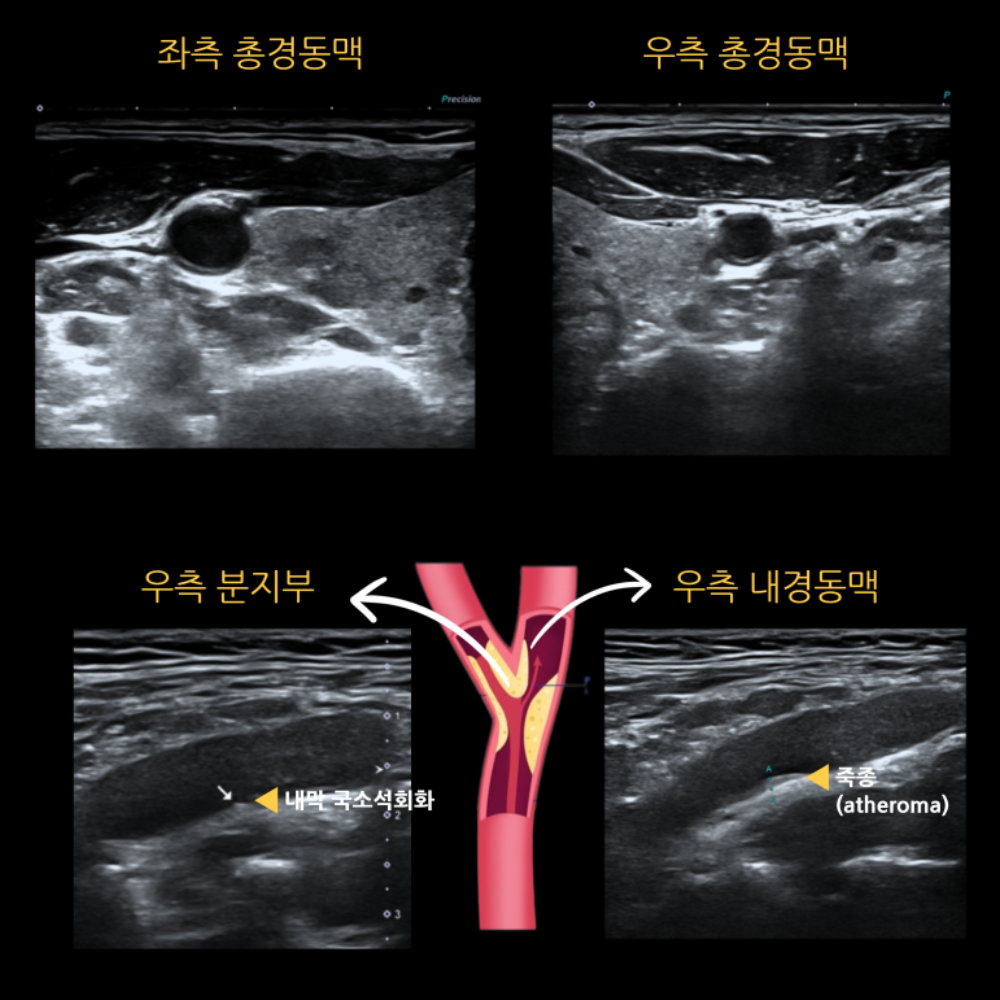

고혈압 환자분의 경동맥 초음파 결과

고혈압 환자 10명 중 3~4명은 합병증이 생기고 나서야 진단받는다고 알려져 있습니다.

그만큼 조기 발견과 치료가 가장 중요합니다.